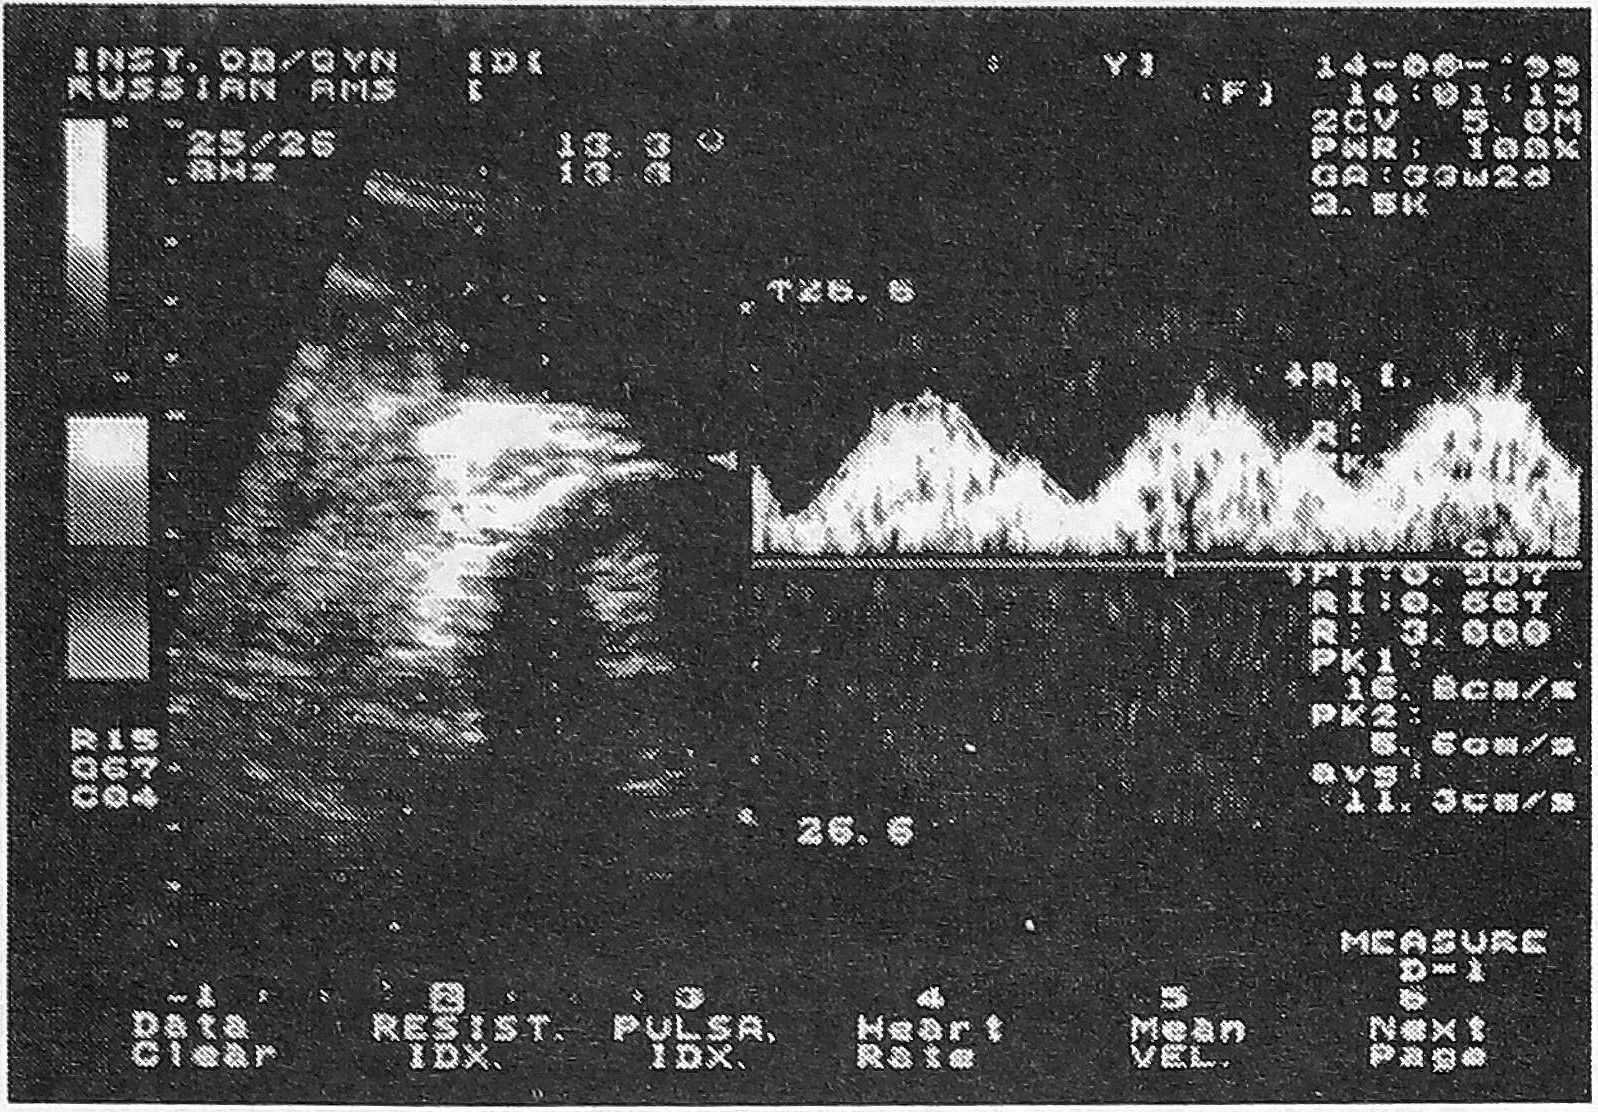

В исследованиях впервые получены данные о кровотоке в яремной вене у плода, по которой осуществляется отток крови из головного мозга. Выявленные особенности становления оттока венозной крови из ЦНС плода совпадают со сроками активности нейроонтогенеза. Так, I-й этап становления гемоциркуляции в яремной вене наблюдается до 32-й недели беременности. В этот период в момент сокращения предсердий плода кровь движется от сердца (регистрируется отрицательный компонент кровотока) (рис. 6). После 32-й недели беременности начинается II этап становления кровотока в яремной вене, во время которого кровь из головного мозга плода оттекает непрерывно на протяжении всех фаз сердечного цикла (рис. 7).

Рис. 6. Допплерограмма кровотока в яремной вене у плода при сроке беременности 24 недели. РК - ретроградный кровоток.